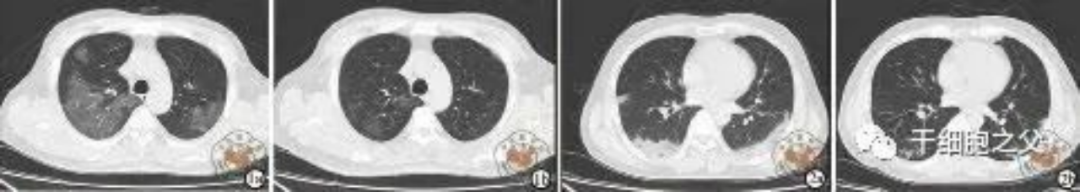

如圖所示,1a-1b:細(xì)胞輸注后,炎癥指標(biāo)改善,復(fù)查胸部CT提示雙肺病灶較前吸收,呼吸道癥狀改善,新型冠狀病毒核酸檢測(cè)連續(xù)2次陰性,治愈出院。圖2a-2b:2次干細(xì)胞輸注后炎癥指標(biāo)改善,復(fù)查時(shí)氧合指數(shù)升高至301 mmHg,胸部CT提示雙肺病灶較前吸收,患者呼吸道癥狀改善,新型冠狀病毒核酸檢測(cè)連續(xù)2次陰性,治愈出院。

與安慰劑組相比,人臍帶間充質(zhì)干細(xì)胞治療組全肺病變體積改善了10.8%,并且人臍帶間充質(zhì)干細(xì)胞治療組在每一個(gè)隨訪(fǎng)節(jié)點(diǎn)都顯示出固體組分病變體積比例減少。此外,人臍帶間充質(zhì)干細(xì)胞組有17.9%的患者在12個(gè)月時(shí)CT圖像變?yōu)檎?,而安慰劑組沒(méi)有。

每次隨訪(fǎng)時(shí)發(fā)現(xiàn),人臍帶間充質(zhì)干細(xì)胞組的相關(guān)癥狀發(fā)生率均低于安慰劑組,中和抗體均為陽(yáng)性,中位抑制率分別為61.6%和67.6%。兩組術(shù)后1年隨訪(fǎng)不良事件及12個(gè)月腫瘤標(biāo)志物比較無(wú)顯著性差異。目前的研究表明,在12個(gè)月的隨訪(fǎng)中,CT圖像所發(fā)現(xiàn)的肺部病變只有在人臍帶間充質(zhì)干細(xì)胞治療的患者中才能完全解決。